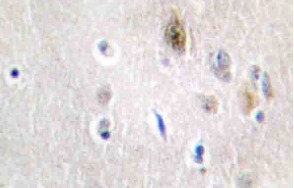

Supportive validation

- Submitted by

- Acris Antibodies GmbH (provider)

- Main image

- Experimental details

- Immunohistochemistry (IHC) analyzes of Tra-2alpha antibody (Cat.-No.: AP20440PU-N) in paraffin-embedded human brain tissue.